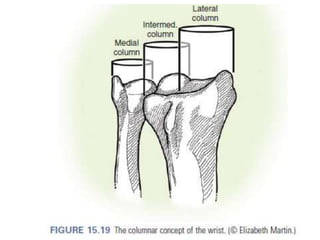

Estabilización de fragmento

• Estiloides

piedra angular .

• Borde volar del

radio

• C dorsal y

palmares de la

carilla lunar del

• La cavidad

Sigmoidea

Estabilización de fragmento •Estiloides piedra angular . • Borde volar del radio • C dorsal y palmares de la carilla lunar del radio • La cavidad Sigmoidea